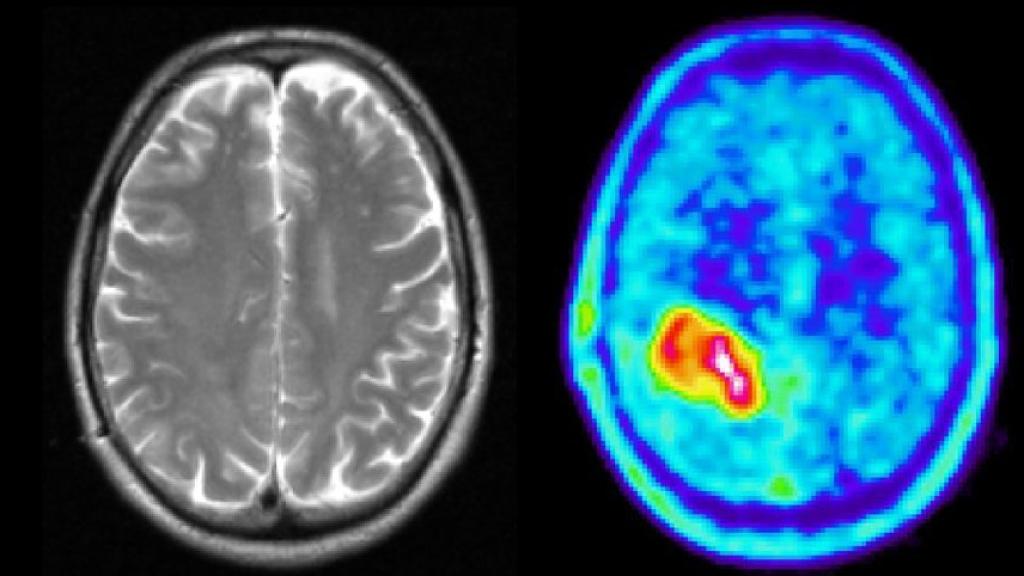

Los gliomas son uno de los tumores cerebrales más agresivos que existen y responsables del 7 por ciento de las muertes por cáncer; un equipo de científicos ha descubierto ahora la conexión que tienen con las enfermedades neurodegenerativas y ha abierto la puerta al diseño de nuevas terapias contra ese tipo de cáncer.

Aunque suponen solo el dos por ciento de los tumores cerebrales, los gliomas causan el 7 por ciento de las muertes por cáncer, ha recordado el Instituto de Salud Carlos III, que ha detallado que esta patología es además resistente a la quimioterapia y a la radioterapia y ha destacado por ello la importancia del descubrimiento como punto de partida "muy importante" para diseñar nuevas estrategias terapéuticas.

Los científicos están ahora revisando muestras de otros ensayos clínicos para ver posibles correlaciones con sus resultados; trabajando con radiólogos para encontrar puntos de unión con los datos de las resonancias magnéticas de los pacientes; y con las empresas farmacéuticas que distribuyen los derivados de los taxanos que sean capaces de llegar al cerebro, para comprobar su interés en un posible ensayo clínico con pacientes con glioma, ha informado Pilar García.